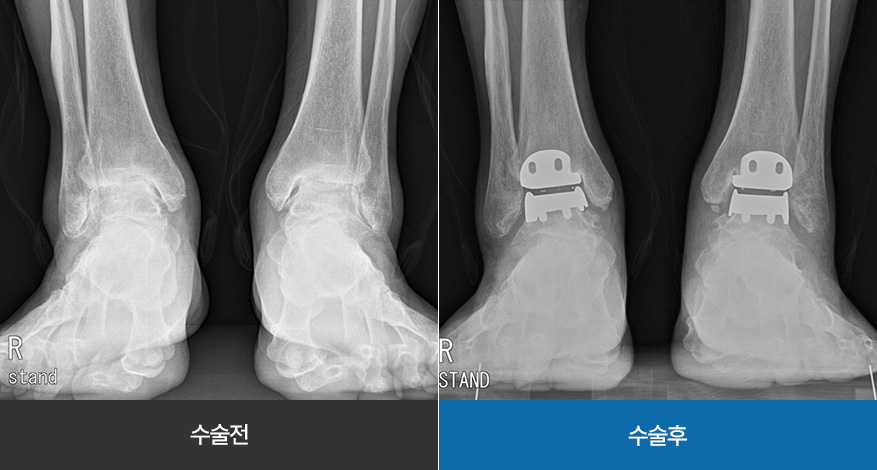

발목 인공관절 수술은 말기 발목 관절염(4단계) 환자에게 시행하는 최종적인 치료 방법 중 하나입니다.

관절의 기능을 잃은 연골을 깎아 인공관절을 삽입하여 통증은 완화시켜주고 발목이 제 기능을 할 수 있도록 도와줍니다. (4~5일간의 입원 기간 목표)